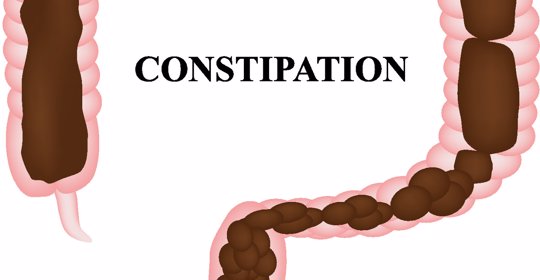

孕期便秘:注意事項與藥物治療

孕期便秘:飲食調整、腹部按摩、適量運動及中藥調理

孕期便秘:枳實、厚朴、芒硝、火麻仁

孕期便秘:原因與非藥物治療方法

孕期便秘:輕柔按摩與中藥外敷